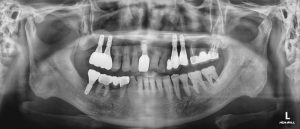

인덕원임플란트 성공적인 식립을 위해

인덕원임플란트 성공적인 식립을 위해 인덕원 부근에서 임플란트 치과를 찾고 계신가요? 임플란트는 한 번 식립하면 10년 이상 사용할 수 있으며 전체 구강 건강을 위해 중요한 시술입니다. 단순히 ‘가까운 곳’이나 ‘저렴한 곳’만...